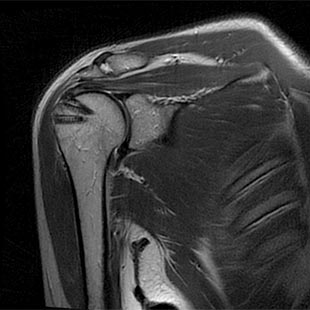

Nach Rekonstruktion mit Fadenankern

Aufgrund der zunehmenden Verbesserung der orthopädischen Techniken und der von der Industrie entwickelten Instrumentarien ist es in den meisten Fällen möglich eine minimalinvasive (arthroskopische) Naht der Rotatorenmanschette über kleine Hautschnitte durchzuführen. Nur in absoluten Ausnahmefällen ist ein mini-open-Zugang (etwa größerer Schnitt) zum Schultergelenk erforderlich. Die arthroskopische Naht schont den Weichteilmantel des Schultergelenkes, verringert den Schmerz nach der Operation und verkürzt die nach der Operation notwendige Rehabilitation. Auch bei älteren Patienten können größere Rotatorenmanschettenrisse, soweit es die Rissform zulässt, behandelt werden. Zur Befestigung der Rotatorenmanschette verwenden wir bioresorbierbare Anker. Eine Materialentfernung ist nicht erforderlich.